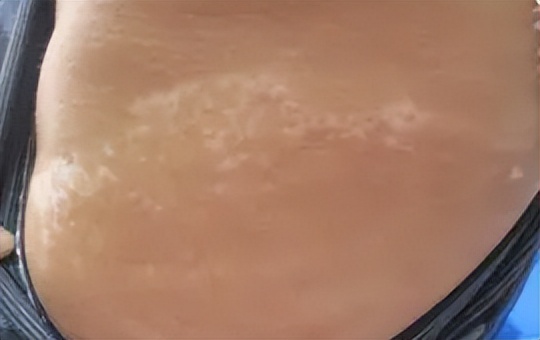

来院治疗四次后的照片

四周后小许白斑部位表现为粉红,与正常皮肤交界处界线清晰,白斑区域内有均匀黄豆大小圆点状皮肤恢复正常肤色,wood灯下检测隐形白斑消失,采用三维皮肤CT再次检查皮肤基底层,对比首次白斑部位黑色素细胞的取像,发现有明显的黑色素细胞环修复和增加迹象。多种迹象表明近一个月的治疗有效,白斑趋于稳定并且有黑色素细胞生成。